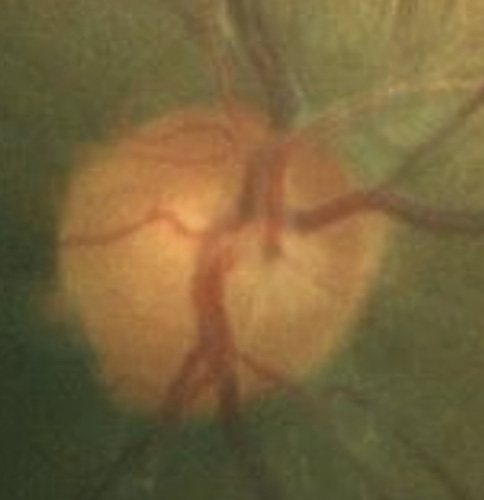

A 46-year-old African American male presents for glaucoma quarterly monitoring. Medical history is positive for hypertension controlled with 50 mg hydrochlorothiazide and reports no diagnosis of diabetes mellitus or known drug allergies. Ocular history is positive for progressive myopia bilaterally and pigment dispersion syndrome converting to pigmentary glaucoma right eye mild, left eye moderate with treatment initiated in September of 2016. The pigmentary glaucoma was treated with 0.005% latanoprost in both eyes every evening. There was positive family history of glaucoma (patient’s father). Best corrected visual acuity was measured at 20/25 in each eye. Pupillary assessment revealed a stable 1+ afferent pupillary defect in the left eye. Confrontation fields were full to finger count in the right eye and superonasal constriction in the left eye. Extraocular motilities were full with no restrictions or report of diplopia in both eyes. Slit lamp examination is remarkable for a Krukenberg spindle (Figure 4) bilaterally and a Zentmeyer line (Figure 5) in the left eye. Intraocular pressures at 3:30 pm via GAT measured 18 mmHg right eye, 23 mmHg left eye. Gonioscopy was performed and revealed open angles to ciliary body with a concave iris configuration and 4+ trabecular meshwork pigmentation (Figure 6) and the posterior corneal surface. There was no pigment attached to the anterior lens surface. The highest recorded intraocular pressures prior to treatment were 27 mmHg right eye & 35 mmHg left eye. CCT measured 554 microns in the right eye and 538 microns left eye. Optic nerve head assessment revealed bilateral intact neuroretinal rims with vertical elongation greater in the left eye than the right with inferior neuroretinal rim thinning in the left eye (Figure 7).

Bild 7: Fall 2 – (a) Sehnervenkopf OD, (b) Sehnervenkopf OS

CD ratios were estimated horizontally/vertically as 0.4/0.5 right eye, 0.6/0.8 left eye. Repeat testing of 24-2 Humphrey Visual Fields (HVF) (Figure 8) and optic nerve head optical coherence tomography (OCT) (Figure 9) were obtained.